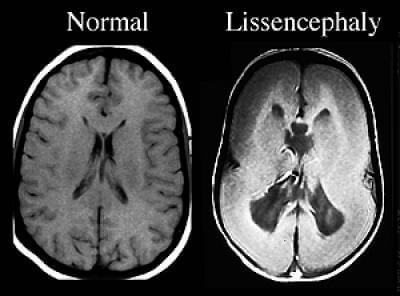

Nichts und niemand hätte diese Lissenzephalie verhindern können. Während der Schwangerschaft läuft einfach die Gyrierung falsch, also die Ausbildung der Gehirnwindungen. Die ist entweder reduziert oder gleich gar nicht vorhanden und so ist das Gehirn dann glatt. Übrigens weiß ich von einer anderen Mama seit gestern, dass auch Koalas ein glattes Gehirn haben. Das wird sicher der neue Spitzname unserer Prinzessin.

Bei unserer Maus kommt hinzu, dass der Balken, also die Verbindung von rechter und linker Gehirnhälfte, auch teilweise fehlt und es kommt zu vielen Fehlschaltungen im Gehirn. Wie einige Kinder mit Miller-Dieker-Syndrom hat auch sie zusätzlich ein West-Syndrom. Das ist eine therapieresistente Form der Epilepsie, die uns in den letzten Monaten ganz gewaltig zu schaffen macht.